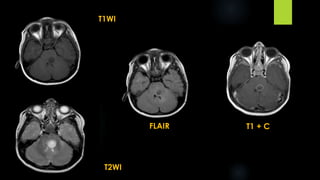

T1WI

DWI T2WI

T1 + C

Differential diagnosis:

 DNET

 Pleomorphic xanthoastrocytoma

 Desmoplastic infantile

ganglioglioma